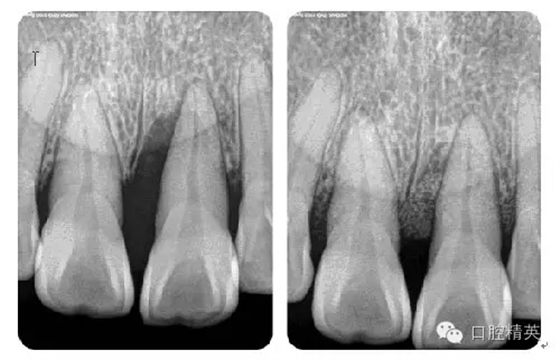

病例1:常規(guī)根管治療

病例2:各型MB2根管

病例3:C型根管

病例4:根管再治療

病例5:遺漏根管再治療

病例6:折斷器械取出

病例7:根尖切除術

病例8:牙周植骨術